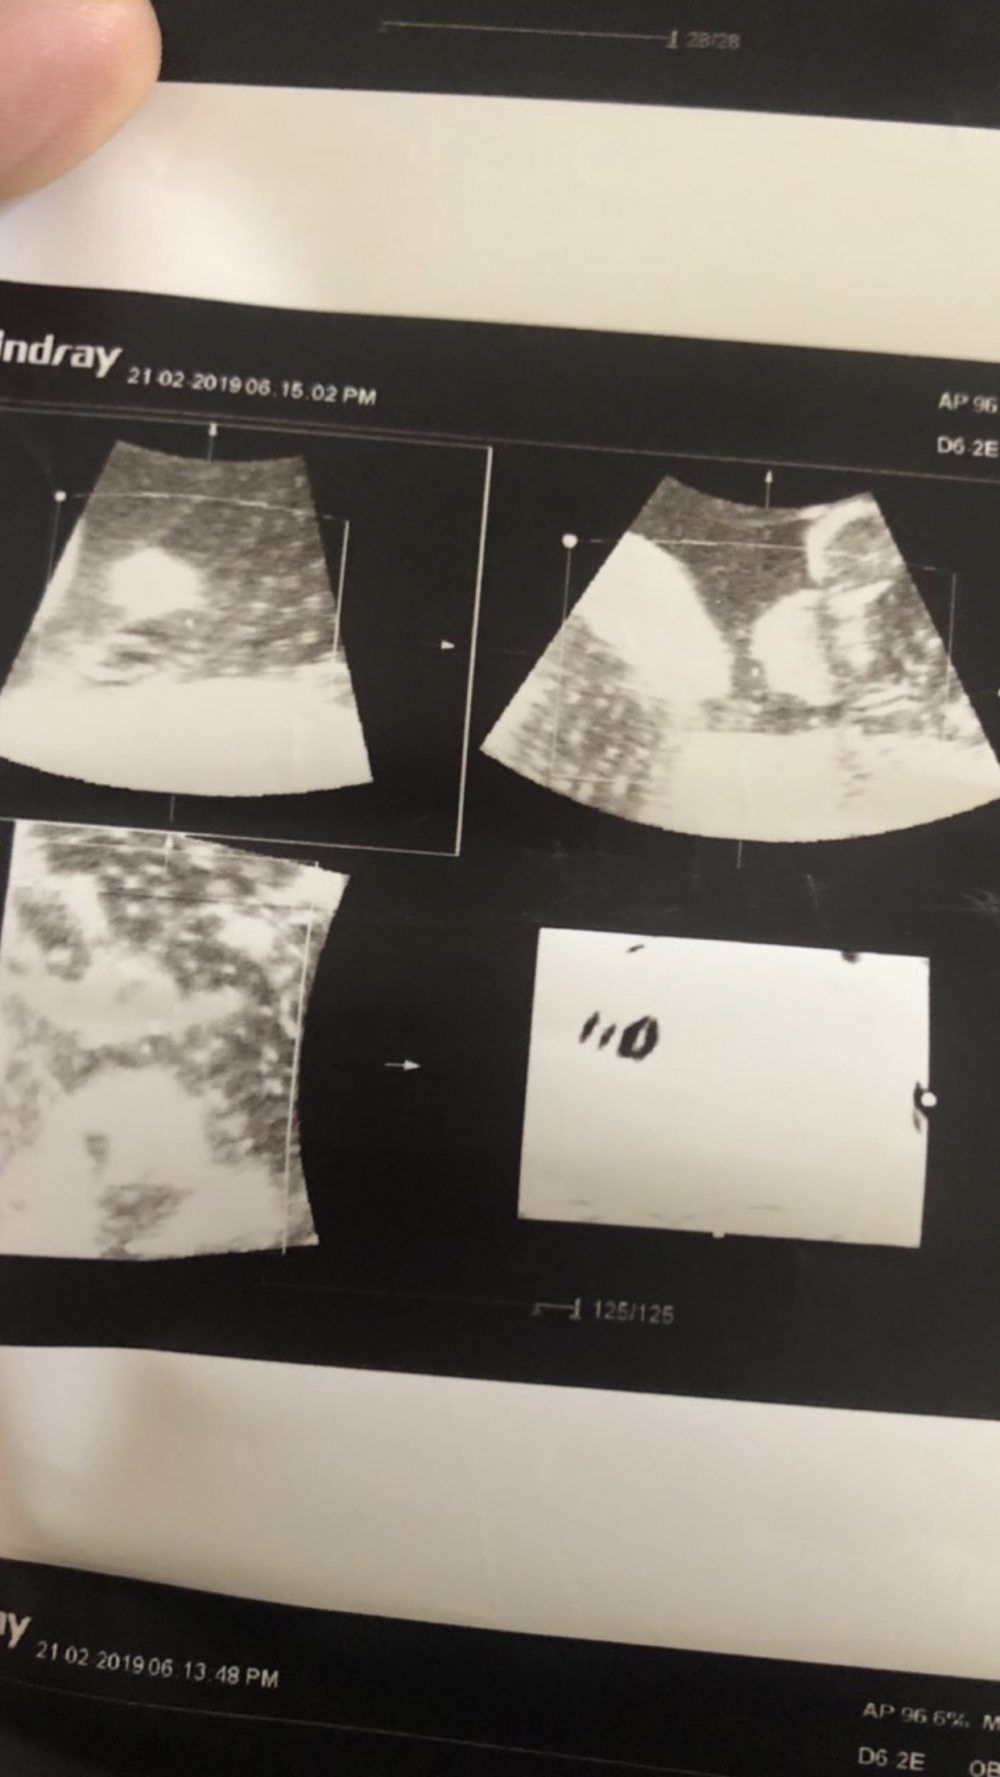

بنات وش تشوفون بنت ولا ولد

الدكتوره ماعطتني الجواب الكافي سويت سونار ثلاثي

مافي شي واضح

ولا صورة تبين مكان العضو

ولا صورة مو واضح منها الجنس